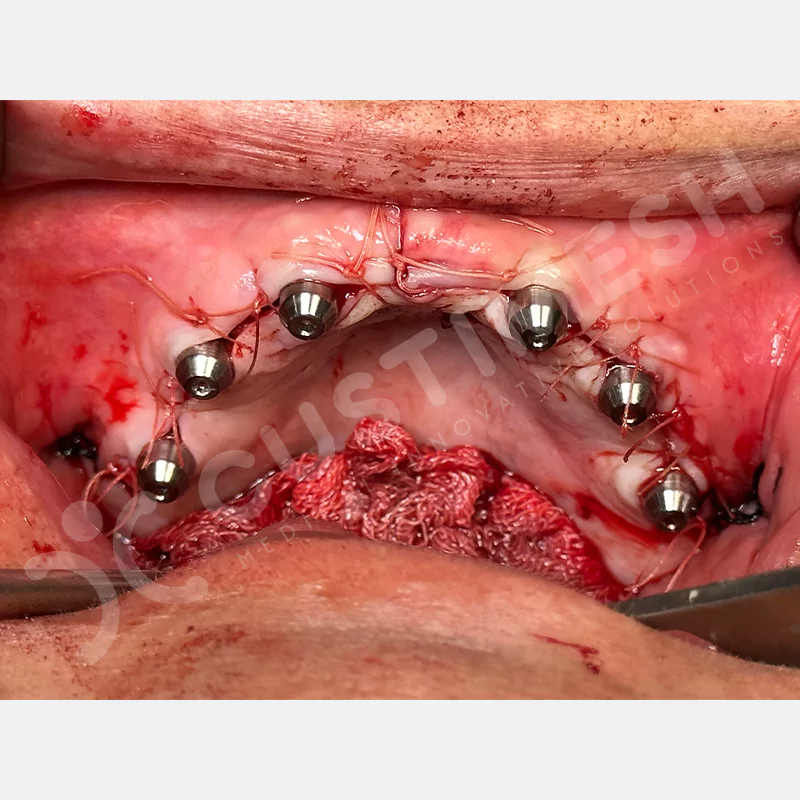

Modern diş hekimliğinde, çene gelişimini tamamlamamış veya ciddi kemik kaybı yaşayan hastalar için kişiye özel titanyum implantlar ile çözüm bulunmaktadır. CAD/CAM teknolojisi ve lazer sinterleme yöntemiyle üretilen bu implantlar, hastanın bireysel anatomik yapısına tam uyum sağlayarak geleneksel implantların uygulanamadığı vakalarda mükemmel bir alternatif oluşturmaktadır. Özellikle ileri derecede kemik kaybı olan hastalar için geliştirilen subperiosteal implantlar, periostun altına yerleştirilerek minimal invaziv bir yaklaşım sunarken, bilgisayarlı tomografi verileri ve sonlu eleman analizleriyle optimize edilmiş tasarımları sayesinde hem estetik hem de fonksiyonel sonuçlar garanti etmektedir. Bu yenilikçi teknoloji, tek seansta implant ve protez uygulamasına imkan vererek hastaların aynı gün doğal gülüşlerine kavuşmalarını sağlarken, kemik greftleme gibi ek işlem ihtiyacını ortadan kaldırarak cerrahi süreci büyük ölçüde kolaylaştırmaktadır. Kişiye özel tasarımı ve üstün biyouyumluluğu sayesinde, daha önce tedavisi mümkün görülmeyen kompleks vakalarda bile başarılı sonuçlar sunan bu implantlar, modern diş hekimliğinde yeni bir çağ açarak hastaların yaşam kalitesini artırmayı hedeflemektedir.

VAKA 1

VAKA 2

VAKA 3

VAKA 4